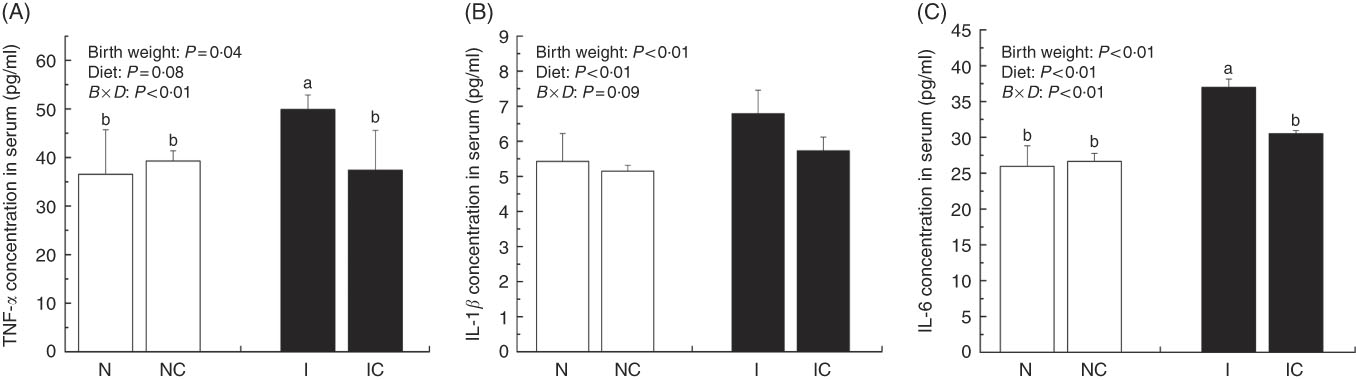

Levels of serum inflammation cytokines

IUGR rats exhibited significantly higher (P<0·05) concentrations of serum TNF-α, IL-1β and IL-6 compared with NBW rats (Fig. 2(A)–(C)). Curcumin supplementation reduced the concentrations of serum TNF-α (P=0·077), IL-1β (P=0·007) and IL-6 (P=0·002) in NBW or IUGR rats. In addition, a birth weight×dietary interaction effect (P<0·05) was noted for concentrations of TNF-α and IL-6 in the liver. There were no significant differences in the concentrations of serum inflammation cytokines among NBW, NC and IC groups (P>0·05).

Fig. 2 Concentrations of TNF-α (A), IL-1β (B) and IL-6 (C) in the serum of normal birth weight rats (N), normal birth weight rats supplemented with curcumin (NC), intra-uterine growth retardation (IUGR) rats (I) and IUGR rats supplemented with curcumin (IC) (12 weeks of age). Values are means (n 6) and standard deviations. ![]() , Normal birth weight;

, Normal birth weight; ![]() , IUGR; B, birth weight; D, diet; B×D, interaction between the corresponding parameters. Data were analysed by using two-way ANOVA.

, IUGR; B, birth weight; D, diet; B×D, interaction between the corresponding parameters. Data were analysed by using two-way ANOVA.

a,b Mean values with unlike letters were significantly different when a significant interaction was observed (P<0·05).

IUGR neonates are associated with a high risk of inflammation and oxidative stress( Reference Tarryadkins, Fernandeztwinn and Hargreaves 28 ). TNF-α is a key immune modulator, which can activate chemotactic cytokines and produce free radicals, leading to oxidative stress( Reference Starke, Daniel and Dumont 32 ). Furthermore, TNF-α, IL-1β and IL-6 have been implicated as prototype pro-inflammatory cytokines in the pathogenesis of sepsis( Reference Deventer 33 ). Higher TNF-α, IL-1β and IL-6 levels were observed in the serum of IUGR rats, which implied that pro-inflammation occurred in the body. Reports had demonstrated that a strong pro-inflammatory bias existed in IUGR with placental insufficiency( Reference Raghupathy, Al-Azemi and Azizieh 8 ). Significantly high concentrations of TNF-α, IL-1β and IL-6 in IUGR rats were significantly decreased after dietary curcumin supplementation, suggesting that curcumin could reduce inflammatory responses in the serum. These results are similar to those of previous studies in cells( Reference Liu, Shang and Li 34 ) and rats( Reference Soetikno, Sari and Veeraveedu 35 ). The liver is an important organ, and liver dysfunction has been observed in IUGR newborn pigs( Reference Junjun, Lixiang and Defa 7 ). The activities of AST and ALT are positively correlated with portal flow( Reference Kuo, Li and Alfrey 36 ). Hepatic ALT is usually located in the cytoplasm, whereas AST is distributed in the cytoplasm and mitochondrial fractions. However, when the structure of the liver is seriously damaged, ALT and AST are released into the circulatory system, resulting in the improvement of ALT and AST activity in the serum( Reference Nyblom, Berggren and Balldin 37 ). In this study, the activities of serum AST and ALT in the IUGR group were higher than those in the NBW group. The increased activities of serum ALT and AST are generally accepted biomarkers for hepatic dysfunction( Reference Tang, Chao and Xing 38 ). The vacuolisation and cell oedema from the histological examination of liver sections were prevalent in hepatocytes of IUGR rats, which revealed histological damage in the liver of IUGR rats. Meanwhile, fat cells also had mild denaturation. Similar to our findings, IUGR fetuses had a higher activity of glutamate oxaloacetate transaminase and impaired liver function than the normal ones( Reference Liu, Lin and Wang 39 ). After curcumin supplementation, the abnormal levels of serum AST and ALT and liver histological damage improved, and these results were not different from those observed in the normal condition. Previous studies had shown that curcumin could significantly reduce the levels of serum AST and ALT( Reference Zhao, Song and Chai 40 ) and liver injury in mice( Reference Zhang, Xu and Zhang 16 ) and rats( Reference Toydemir, Kanter and Erboga 22 ). Our findings indicated that diets supplemented with curcumin attenuated liver injury and inflammation in IUGR rats. Thus, we concluded that the protective effects of curcumin on the liver may be very important in IUGR rats. To investigate the immunomodulatory mechanisms of curcumin, we detected the expressions of the NF-κB and JAK/STAT pathways in the liver. NF-κB is found in cytoplasm bound to IκB. In response to various stimuli, including cytokines, stress and bacterial pathogens, the latent cytoplasmic NF-κB/IκB complex is activated by phosphorylation( Reference Hiscott, Kwon and Genin 41 ). Phosphorylation of IκB induces their ubiquitination, proteosome degradation and, subsequently, NF-κB release and nucleus translocation( Reference Echeverri, Nancy and Mockus 42 ). NF-κB is one of the most ubiquitous eukaryotic transcription factors that regulate the expression of genes associated with control of inflammatory responses, cellular proliferation/growth, cell adhesion and other processes( Reference Chen, Castranova and Shi 43 ). Our results showed that IUGR induced increased levels of phosphorylated IκBα and nuclear NF-κB and decreased levels of cytoplasmic phosphorylated NF-κB in the liver. Similar to our study, Zhong et al.( Reference Zhong, Li and Huang 44 ) also reported that the IκB was activated and the expression of NF-κB was increased by IUGR. These results suggested that the activation of the NF-κB/IκB complex might be related to increased levels of cytokines in IUGR, including TNF-α and IL-1β. The JAK2/STAT3 pathway is known to be involved in the immune response of numerous cytokines, including IL-6, and activated in response to injury( Reference Yang, He and Hao 45 ). Our results demonstrated that IUGR induced high levels of phosphorylated JAK2 and STAT3 in the liver. The activation of the JAK/STAT3 pathway might be the result of increased IL-6 in IUGR rats. Our results also showed that expression levels of Tnfa, Il1b and Il6 were up-regulated in the liver of IUGR rats. Importantly, dietary curcumin supplementation obviously inhibited the phosphorylation levels of the NF-κB pathway and JAK2 in IUGR rats and down-regulated the expression of those downstream genes. These observations supported that curcumin attenuated inflammation through the NF-κB( Reference Soetikno, Sari and Veeraveedu 35 , Reference Surh, Chun and Cha 46 ) and JAK/STAT pathways( Reference Kim, Park and Joe 47 ) in the liver of IUGR rats, which resulted in the negative regulation of cytokines (TNF-α) and pro-inflammatory interleukins (IL-1β and IL-6)( Reference Reyes-Gordillo, Segovia and Shibayama 48 ).